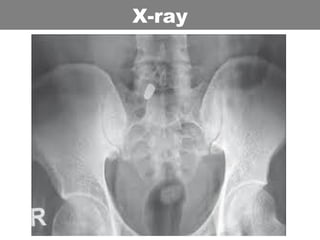

• Xray and CT: Nil

Xray pelvis

X-ray

unit of blood might be lost.

• Open book fracture

• Pelvic binder

• CT if stable

• Theatre